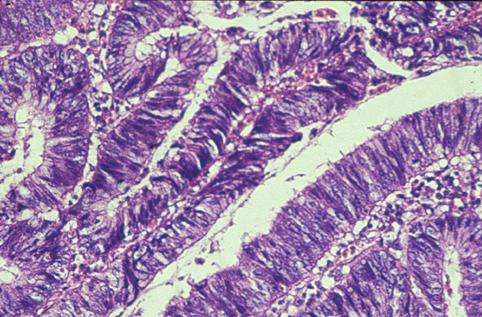

明显可见有粘液产生的直肠绒毛膜上皮肿瘤(腺瘤)

大肠/直肠

病理切片(微观)

0型(表在型)/I型(Is)

40以上

m